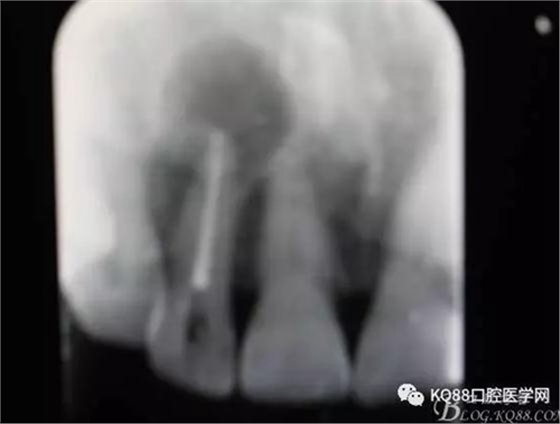

圖1.患者在根管術(shù)前的根尖片影像檢查:12有開(kāi)髓孔,根尖有橢圓形陰影。